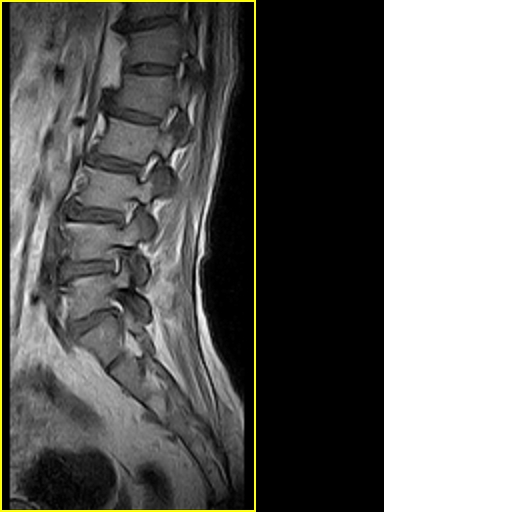

男,78岁,右下肢跛行两月.

腰间盘膨出、黄韧带肥厚、可疑先天性腰椎管狭窄。

退行性骨关节病:增生、椎间盘变性、膨出...

退行性病变:增生、椎间盘变性、膨出[l4-5、l5-s1 椎间盘膨出]

退行性骨关节病:增生、椎间盘变性、膨出..黄韧带肥厚.